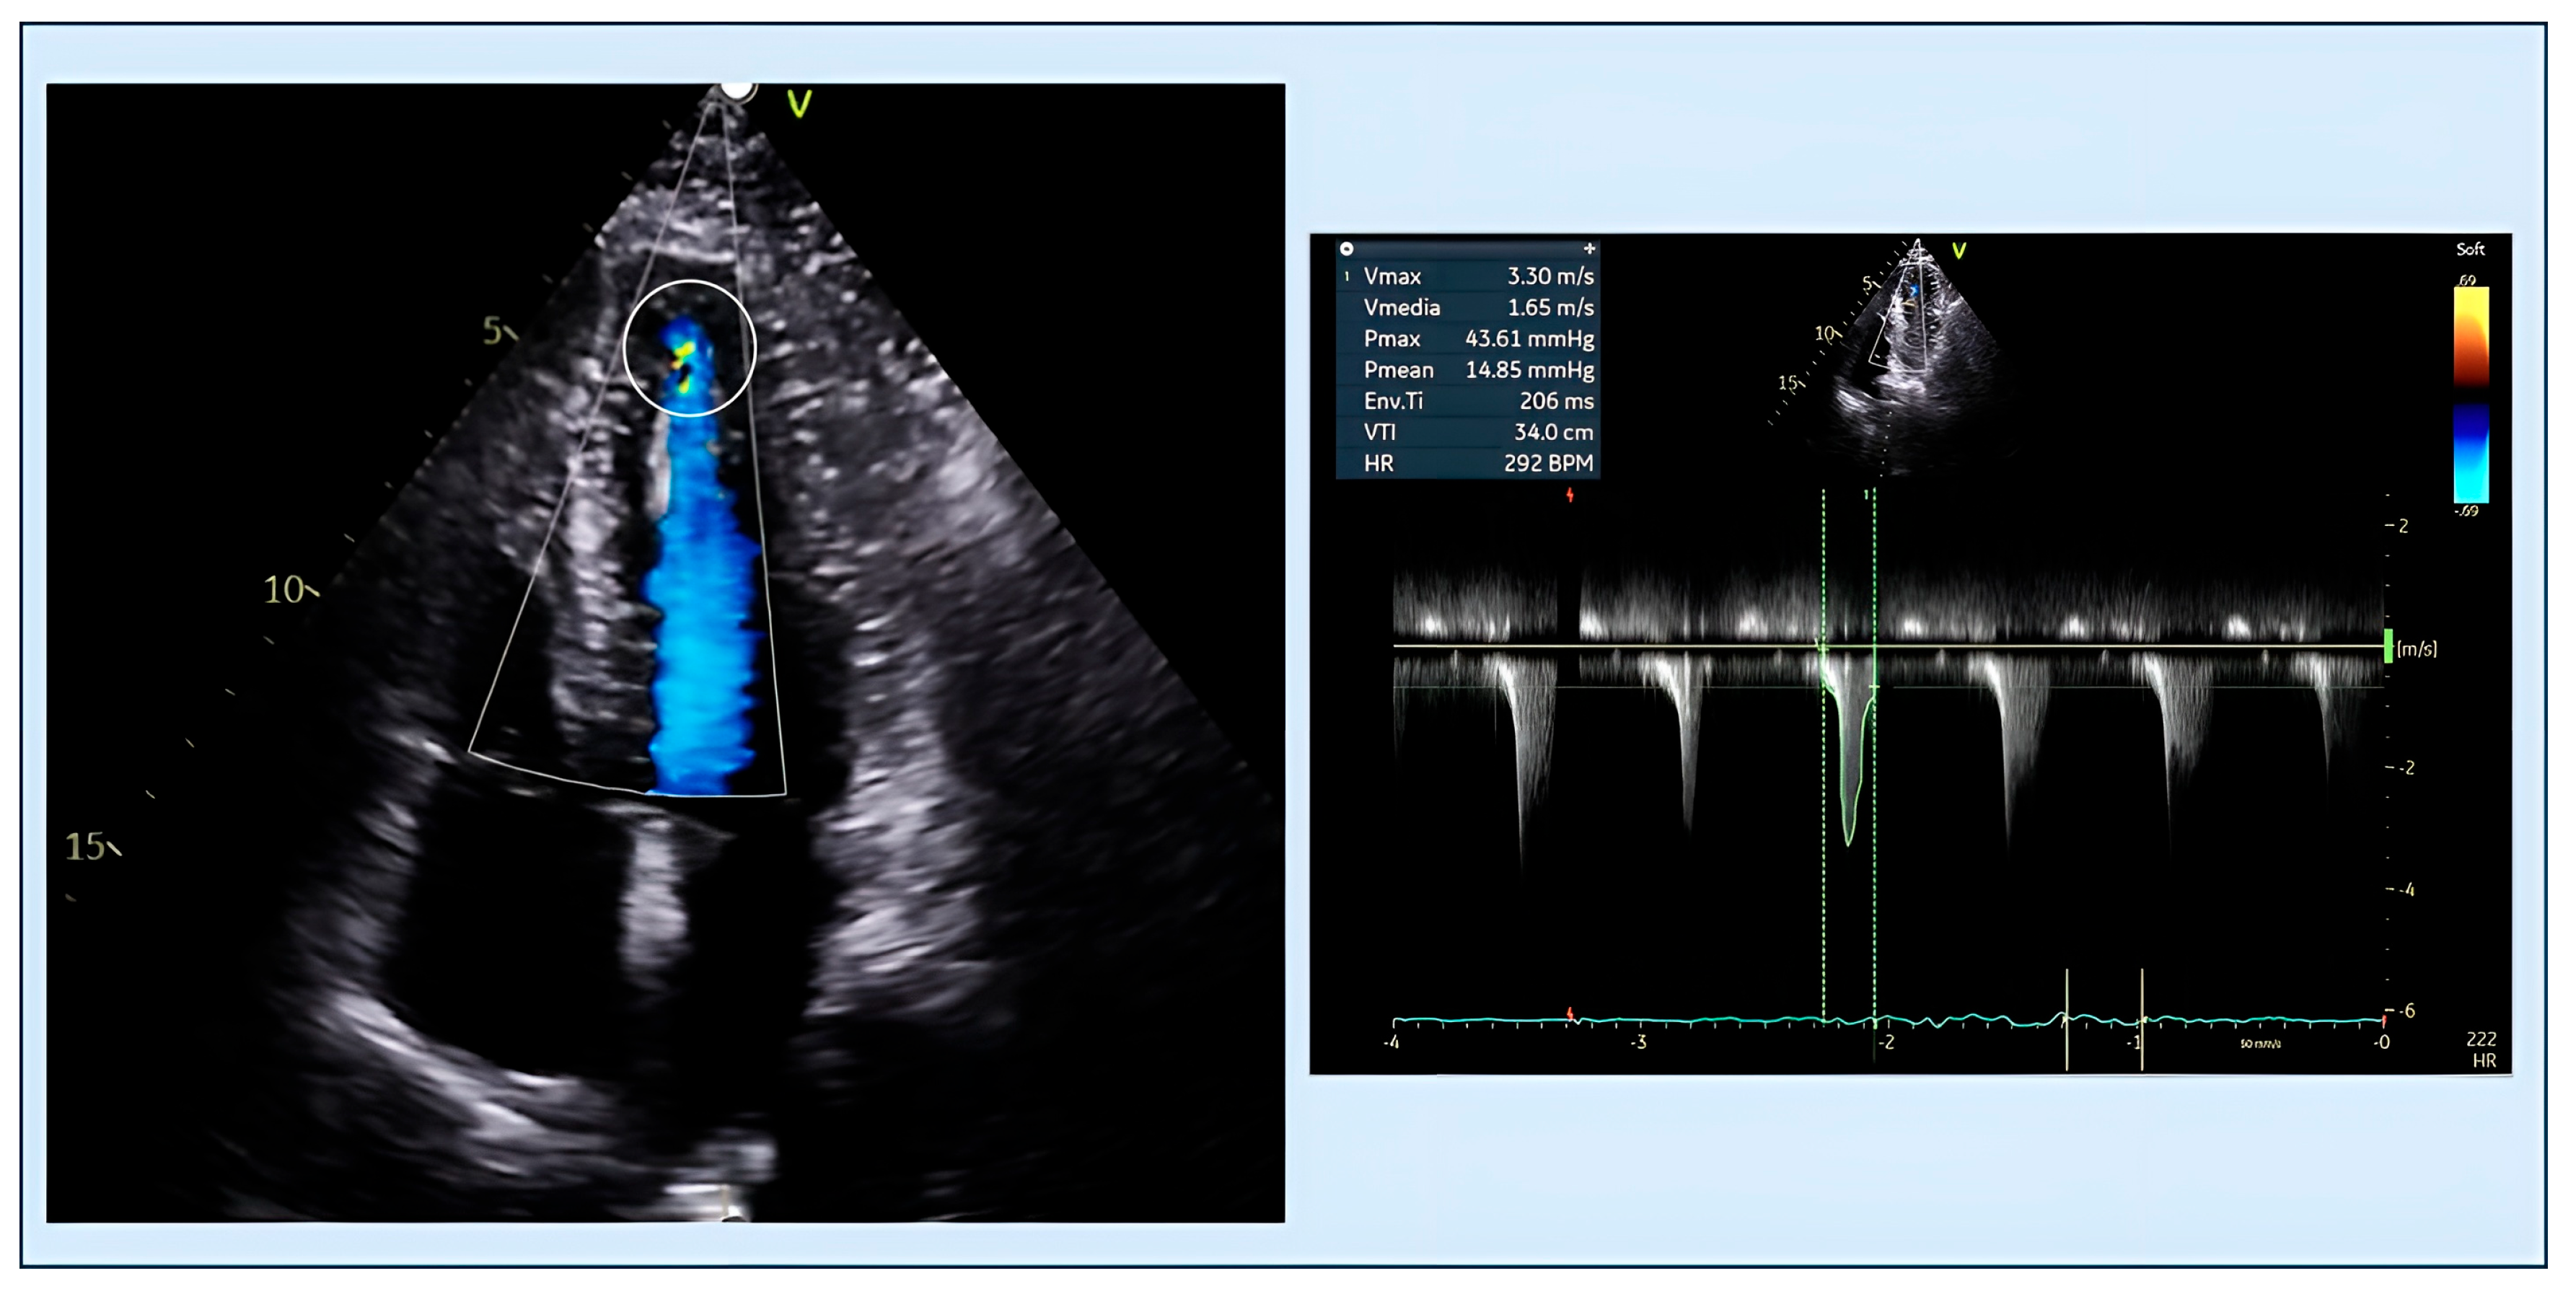

4.1. Obstruction

- Po, J.R.; Kim, B.; Aslam, F.; Arabadjian, M.; Winson, G.; Cantales, D.; Kushner, J.; Kornberg, R.; Sherrid, M.V. Doppler Systolic Signal Void in Hypertrophic Cardiomyopathy: Apical Aneurysm and Severe Obstruction without Elevated Intraventricular Velocities. J. Am. Soc. Echocardiogr. 2015, 28, 1462–1473. [Google Scholar] [CrossRef]

- Nakamura, T.; Kitamura, H.; Furukawa, K.; Matsubara, K.; Katahira, T.; Okamuro, S.; Tsuji, Y.; Takahashi, T.; Kunishige, H.; Katsume, H. Intraventricular flow dynamics in hypertrophic cardiomyopathy with midventricular obstruction investigated by Doppler echocardiography. J. Cardiol. 1989, 19, 455–471. [Google Scholar]

- Rakowski, H.; Sasson, Z.; Wigle, E.D. Echocardiographic and Doppler assessment of hypertrophic cardiomyopathy. J. Am. Soc. Echocardiogr. 1988, 1, 31–47. [Google Scholar] [CrossRef]